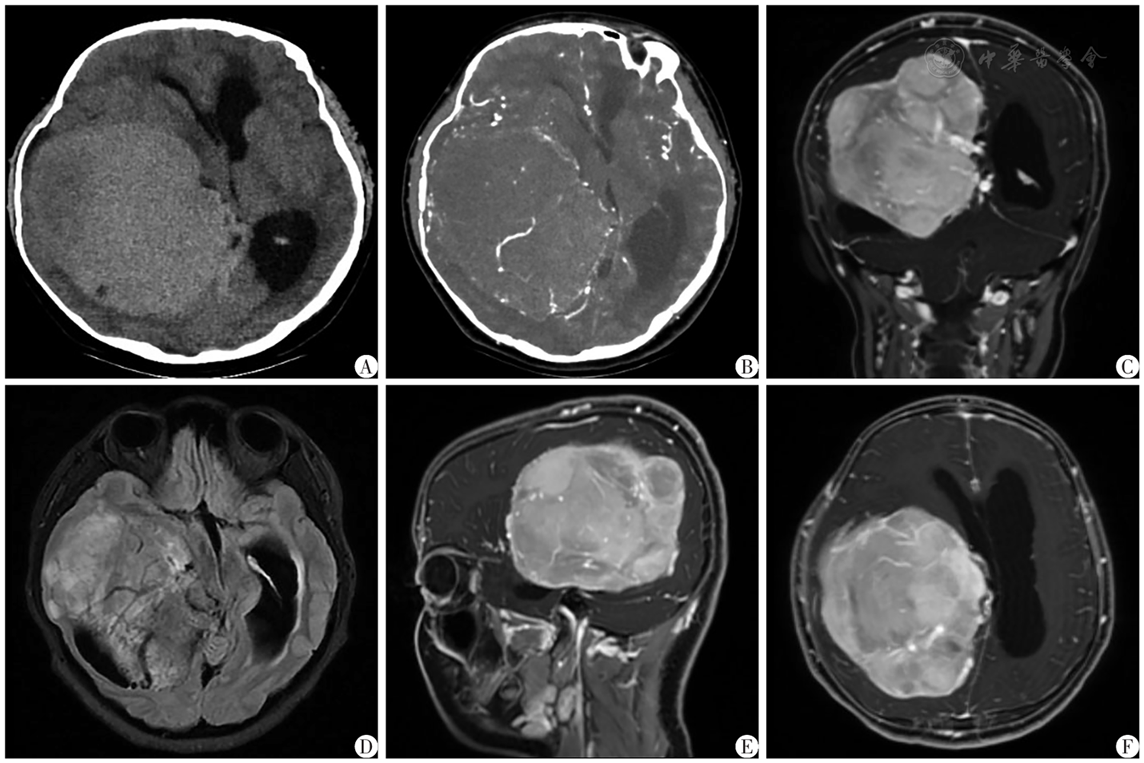

图1 颅内巨大脑膜瘤患儿术前影像学资料A:CT;B:CTA;C:增强MRI T1WI冠状位;D:MRI轴位T2 FLAIR加权;E~F:增强MRI T1WI(E:矢状位;F:轴位)

Fig.1 Preoperative imaging data of a child with intracranial giant meningioma